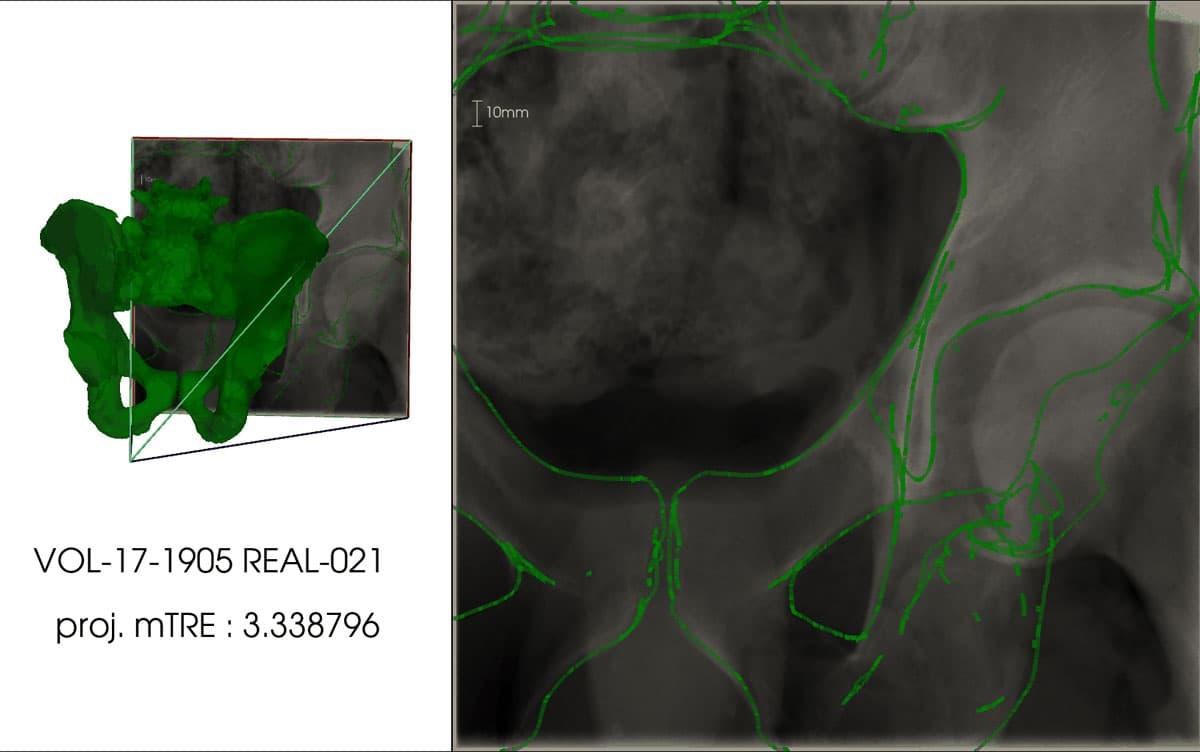

X線透視装置は、整形外科手術において頻繁に使用される医療機器ですが、2次元のX線画像から患部の3次元形状を対応付けるには、医師の経験や知識に多くを頼っているのが現状です。術中に撮影するX線画像と、術前にCTスキャンで取得した3次元モデル(CTモデル)との重ね合わせができれば、医師自身が2次元画像から3次元形状を想像する作業が軽減され、手術に集中できるようになります。このような目的でX線画像とCTモデルを高精度に重ね合わせる際には、「身体の一部だけを大写しした画像(局所画像)でも機能すること」「全自動で処理できること」が不可欠です。そこで本研究では、X線画像のシーン座標を回帰する畳み込みニューラルネットワーク(CNN)を用いて、これらを実現しました。X線撮影カメラの光学中心と画像中の画素を結ぶ直線と、CTモデルとの交点で、シーン座標を定義し、その座標系で3次元点群とその観測位置(2次元座標)の対応関係を自動的に取得可能な手法を考案するとともに、これにより獲得した対応点情報と深層学習を組み合わせることで、局所画像に対しても高精度な重ね合わせに成功しました。

本技術を、骨盤のCTモデルとX線画像の両方が収録されているデータセットを用いて検証した結果、シミュレーションX線画像で3.79mm(標準偏差1.67mm)、実写X線画像で9.65mm(標準偏差4.07mm)の誤差で、X線画像とCTモデルの重ね合わせを達成しました。